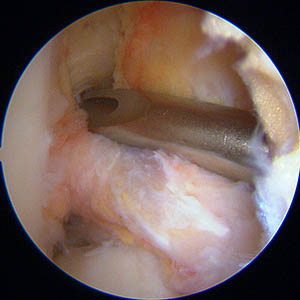

Vue sous arthroscopie : le genou est plié; nous sommes dans l'échancrure et la flèche rouge indique l'insertion du ligament croisé antérieur sur le fémur.

Le crochet est posé sur l'insertion.

L'extrémité du viseur se glisse en arrière au ras de l'os pour prendre appui sur l'os en arrière; l'orifice de sortie de la broche est bien visible.

Une broche est passée, puis une première mèche s'appuyant sur la broche, puis une deuxième de la taille de la greffe.